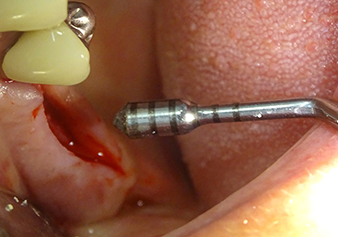

Préparation et augmentation du site implantaire

Après un contrôle intermédiaire (Fig. 4), une étape de préparation ultérieure est exécutée (Fig. 5). Puis on utilise l’insert Z35P hydraulique pour relever la membrane vers la position souhaitée (Fig. 6 et 7). Ensuite, une préparation piézochirurgicale supplémentaire est pratiquée sur le site implantaire, en utilisant pour terminer un burin rotatif et une fraise à épaulement jusqu’à 4,8 mm de diamètre d'implant. Avant l’insertion de l'implant, le matériau d’augmentation (taille de particules env. 0,8-1,6 mm) est introduit sous la membrane de Schneider (Fig. 8).